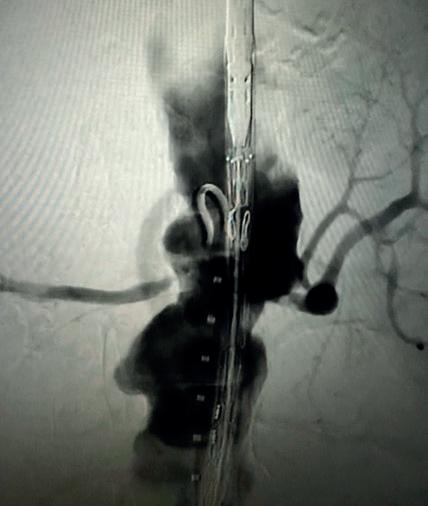

Case 2: The Shockwave M5+ tackles 90% stenosis of the distal SFA

The patient is a 75-year-old man with a history of hypertension, hyperlipidemia, CAD, chronic kidney disease and diabetes mellitus, who presents with a non-healing wound of the right lower extremity for three months. He had undergone diagnostic work—his ankle-brachial index (ABI) was found to be 0.73 with a toe pressure of 50mmhg, and a duplex ultrasound revealed a densely calcified superficial femoral artery (SFA) stenosis of 90%.

He was taken to the cath lab and underwent a right lower-extremity arteriogram. This confirmed a 90% stenosis of the distal SFA, with normal three-vessel run off. Due to the heavy calcium, we opted for a Shockwave M5+ 6x60mm and delivered 200 pulses to the lesion. There was no appreciable residual stenosis at the completion of the procedure, and his post-procedure ABI improved to 1.

This is a great example of how IVL can be used as a standalone therapy without the need for adjunctive treatment.

Figure 1. Pre-procedural angiogram

Figure 2. Pre-procedural angiogram